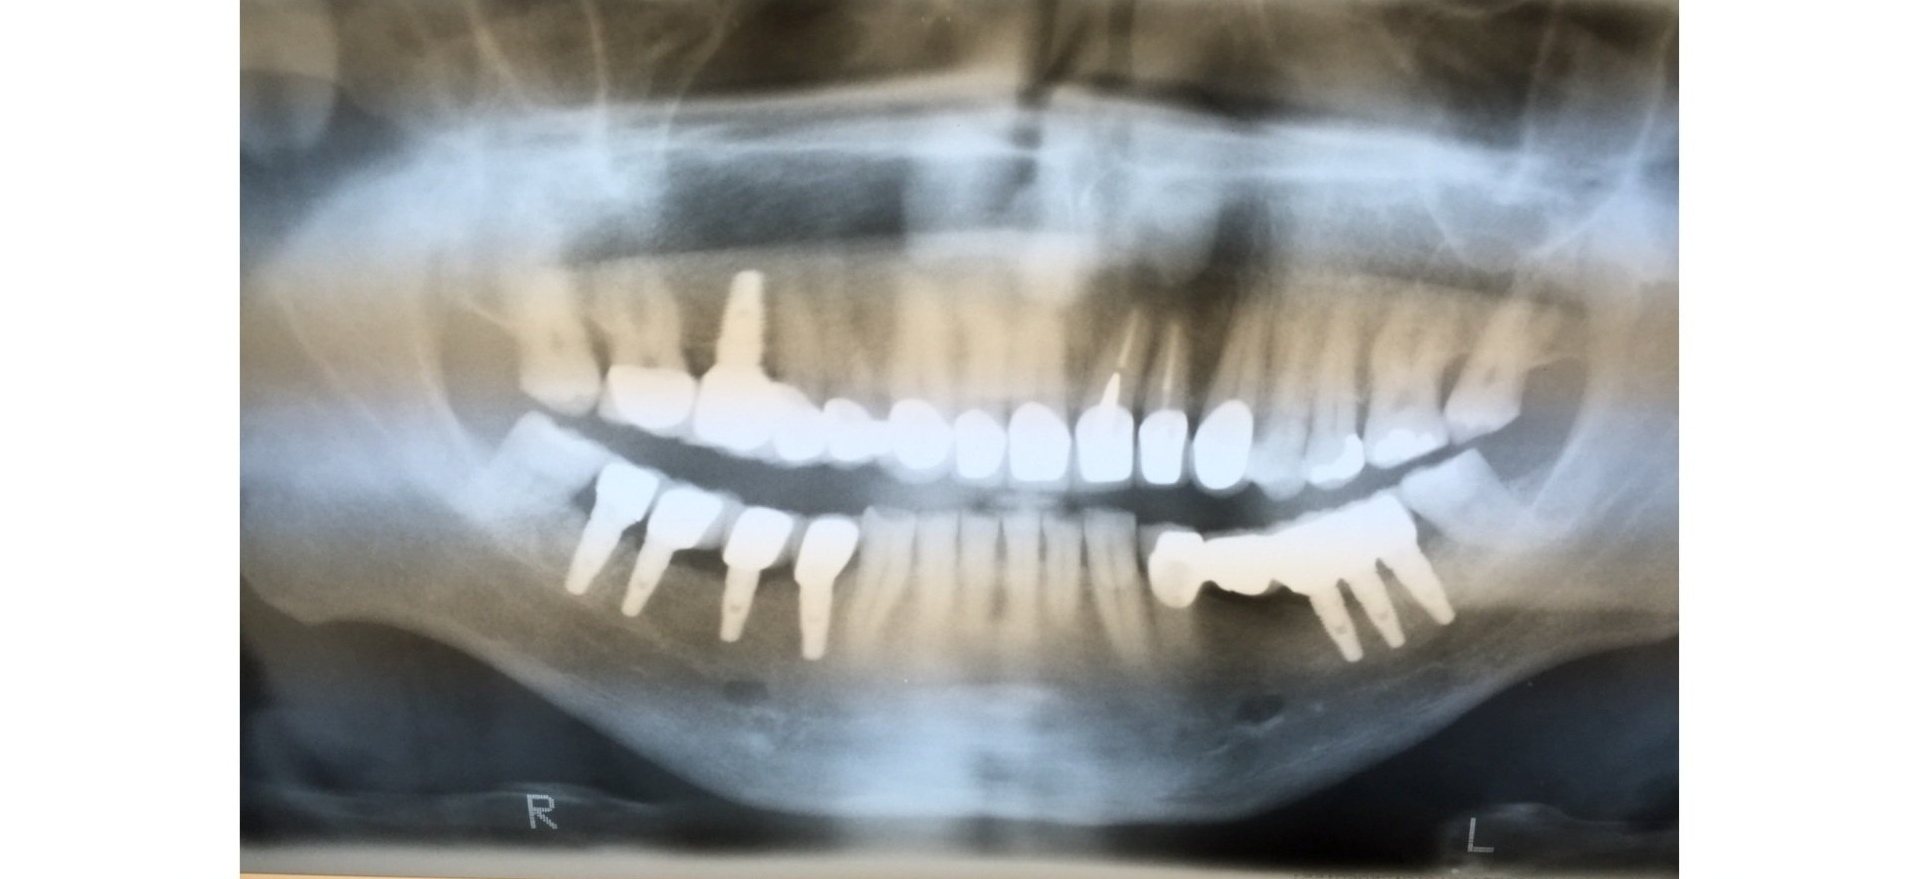

Gallery

A healthy and radiant smile is the goal. We offer dental care and

information on how you can prevent any diseases.

Extreme Cases